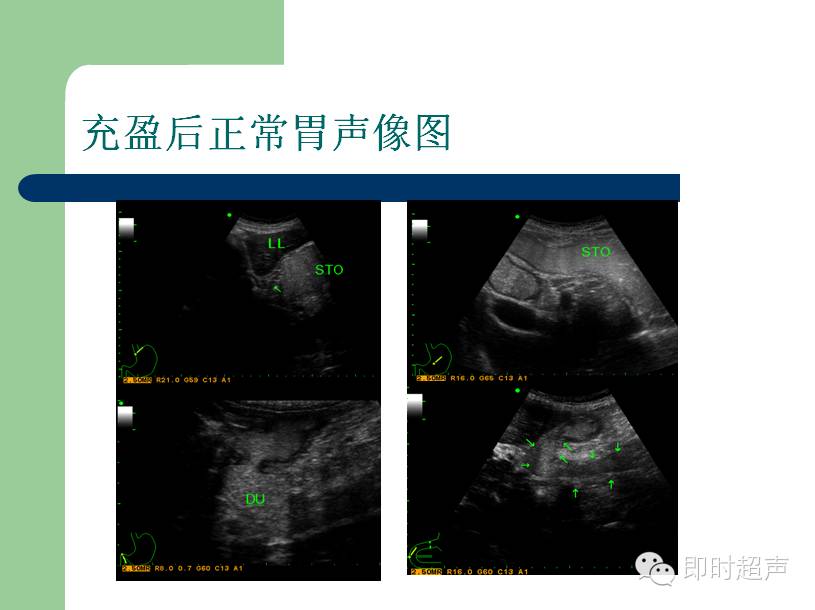

超声下的胃

来源:即时超声